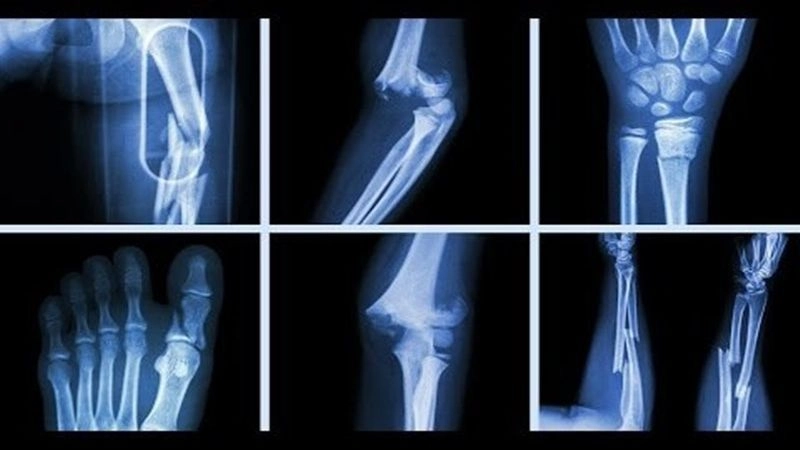

Các vị trí dễ bị gãy xương

Gãy xương sườn: thường xảy ra do chấn thương ở ngực khi bị ngã, tai nạn xe cộ hoặc lúc chơi thể thao, tai nạn xe, lúc chơi thể thao, quá trình sinh mổ bác sĩ có thể phải xoay thai để đảm bảo an toàn cho trẻ sơ sinh, vô tình tạo áp lực lên xương sườn và gây gãy…

Gãy xương đòn: nguyên nhân phổ biến nhất gây ra tình trạng này là ngã chống tay. Lúc này, vai va chạm mạnh trực tiếp gây gãy hoặc gián tiếp gãy trong tư thế duỗi khuỷu, dạng vai

Gãy xương cẳng tay: xuất hiện khi chịu lực trực tiếp như bị đánh, tai nạn giao thông (nguyên nhân trực tiếp), duỗi thẳng tay ra để chống khi (nguyên nhân gián tiếp)…

Gãy xương cẳng chân: xảy ra do tai nạn lao động, tai nạn giao thông, chấn thương thể thao, các bệnh lý về xương…